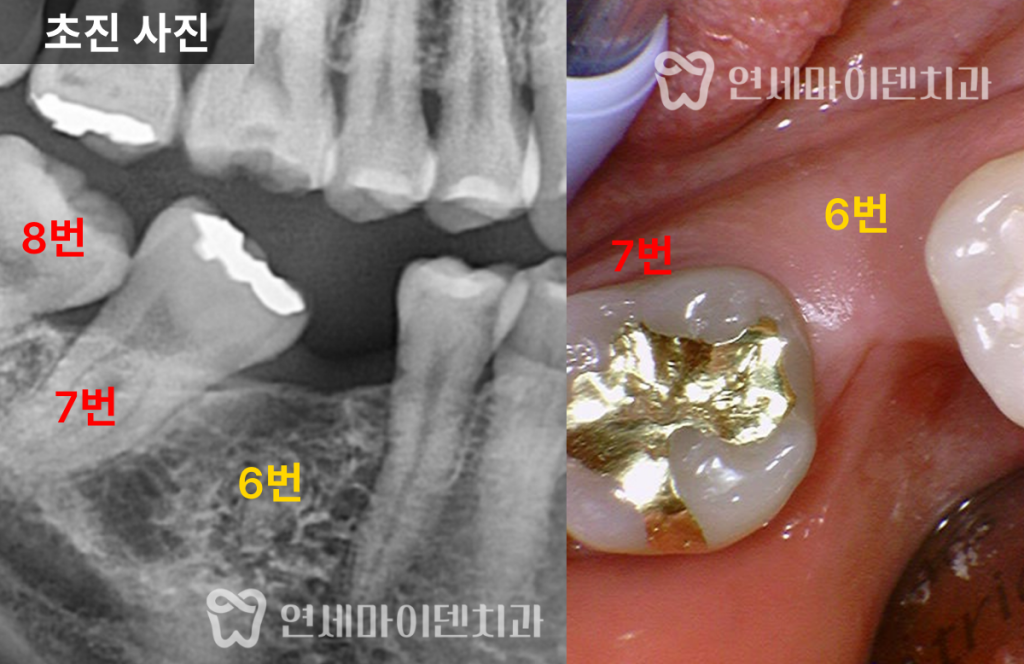

임플란트 공간이 부족했던 초기 상태

해당 환자분은 오른쪽 아래 6번 어금니를

오래전에 발치하신 분으로,

그 결과 뒤쪽의 7번 어금니와 8번 사랑니가

앞으로 기울어져 있었습니다.

이로 인해 임플란트를 식립할 공간이 부족한 상태였고,

보철만으로는 치료가 불가능했습니다.

파노라마 사진을 통해 확인한 결과,

- 6번 치아 부위의 공간이 심하게 좁아져 있었으며

- 위아래 사랑니는 모두 자라 있었고, 일부는 충치가 심했습니다.

특히 오른쪽 아래 사랑니(8번)는

앞 어금니를 제자리로 되돌리는 데 방해가 되어,

공간 확보를 위해 사랑니 발치 후

부분교정 치료를 진행하기로 하였습니다.